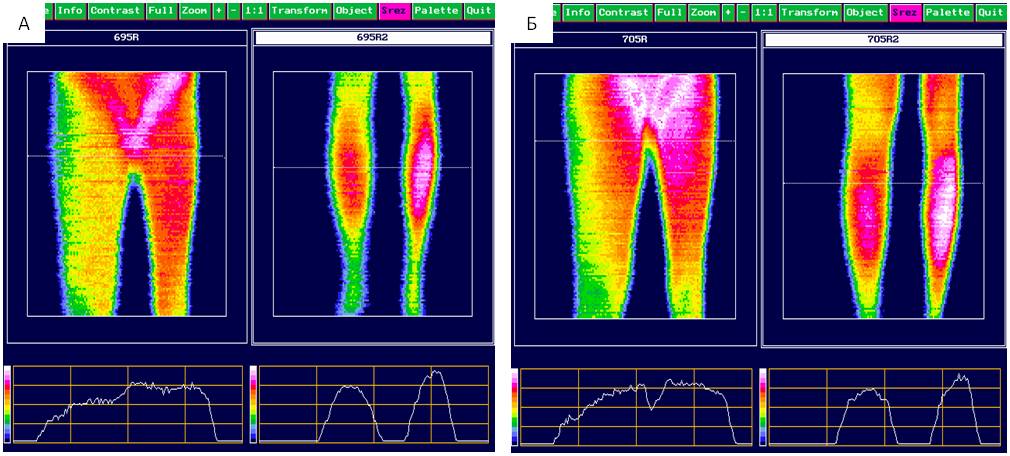

With a high level of objectification, the following changes of the quantitative parameters of infrared radiation of a pathologically altered limb were obtained: left inguinal region — 39.02 ± 0.17°С, popliteal region 37.86 ± 0.13°С, respective regions on the right — 37.93 ± 0.16°С and 38.96 ± 0.19°С. The thermal asymmetry was characterized by peculiarities of arrangement of vessel trunks and innervation of the limb (Table 4). Evaluation of thermography parameters of LL showed increase in the level of IR radiation only in Group 2. Increase (р < 0.001) in the area of hyperthermia in the distal part of lower legs and along the inner surface of thighs was recorded evidencing improvement of microcirculation (Figure 1).

Fig. 1. Clinical example: Thermograms of lower limbs of a female patient S., 58 years old, with III stage secondary lymphedema before (A) and after (B) comprehensive treatment.